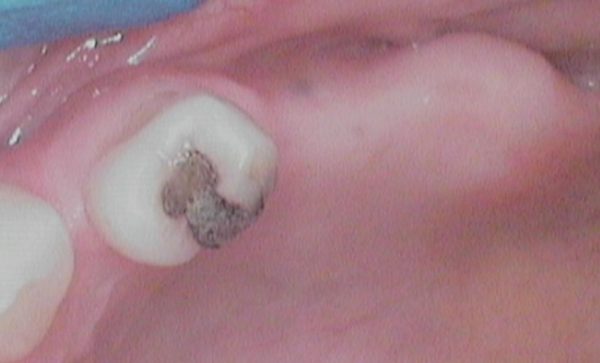

Case 48